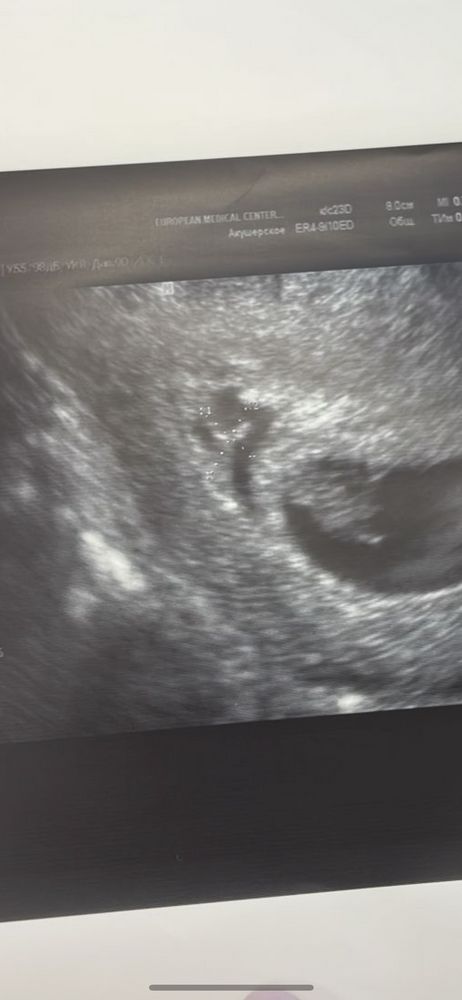

Медикаменты, витамины, процедурыВчера была на узи, увидели гематомку. Небольшая , но все таки есть . Уже как 2 дня пью транексам и отменила кардиомагнил 75мг. к врачу только через 10 дней…..В выписке она писала что на период выделений кардиомагнил отменять на 4 дня. А дальше как быть? Не опасно его возвращать при гематоме?

вы уверены, что это гематома? их часто ставят, мне тоже в ЕМС (!!) сказали, что гематома, врач который первый раз меня видела. Потом мой репродуктолог и гинеколог сказали, что это бред. Это какой-то синус в эндометрии был и до сих пор наверное есть

«Нет таких диагнозов. И гематом 8х9 мм. Это не гематома это обычный синус в эндометрии»

«сосудистый»

коммент моего врача